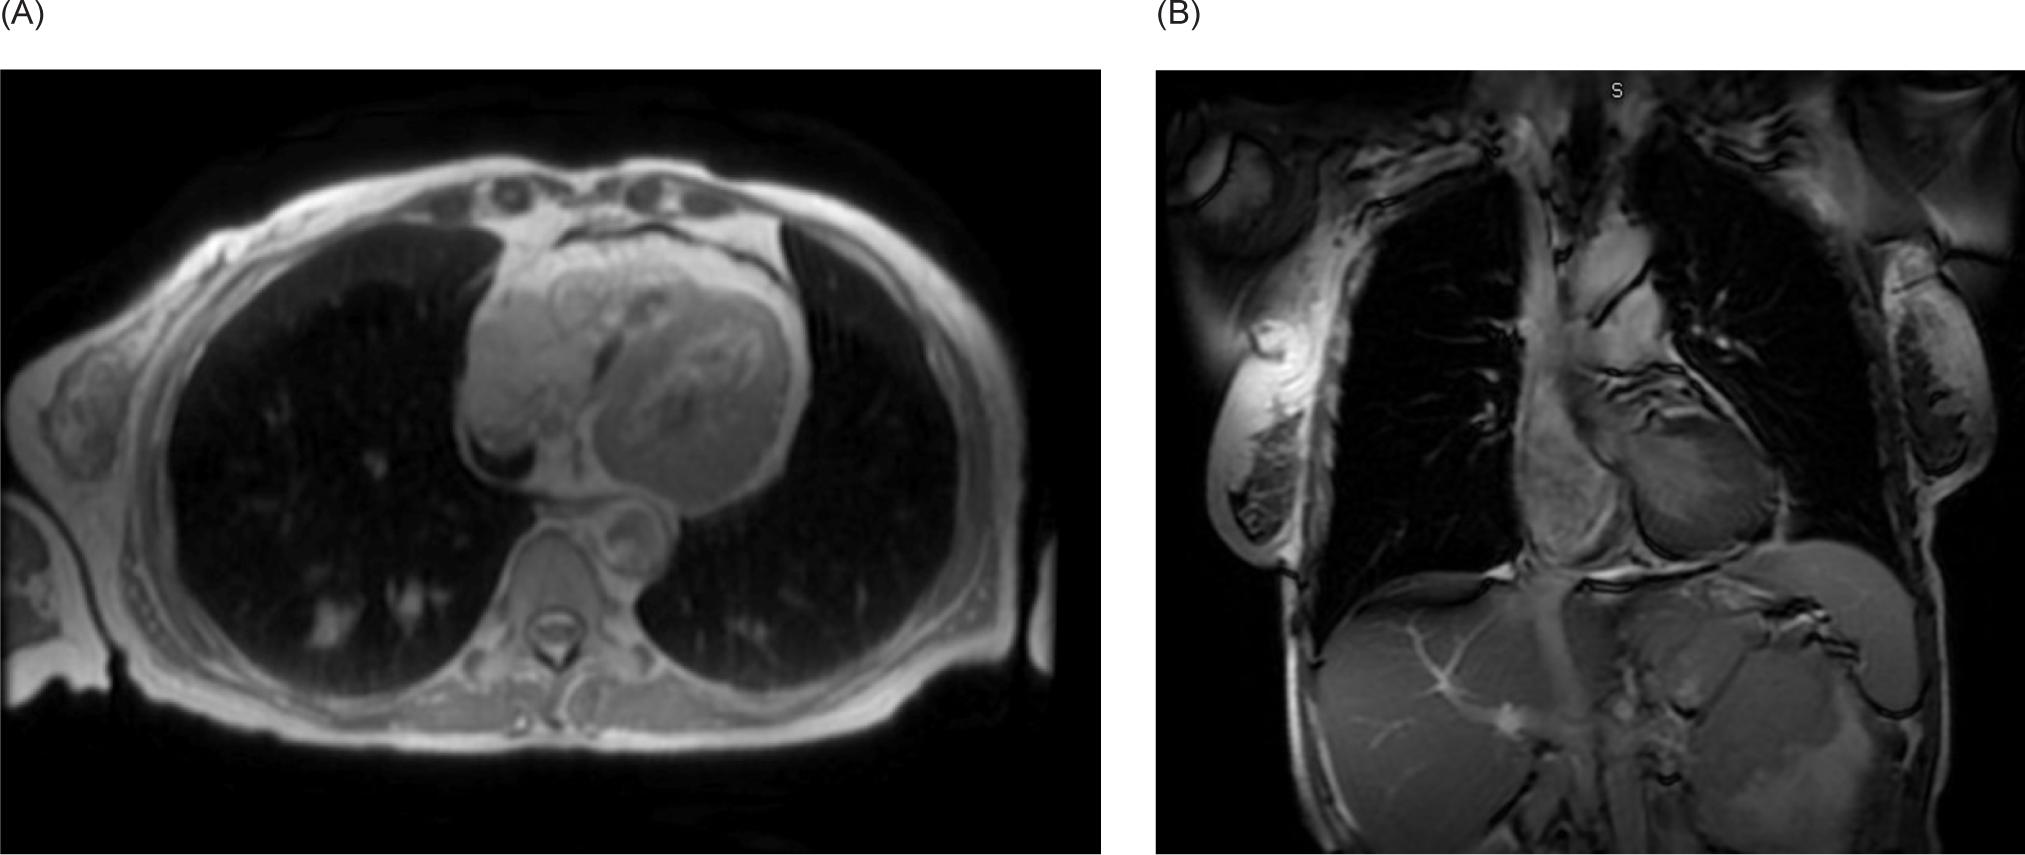

A 59-year-old female smoker with history of hypertension and hyperlipidemia who was screened for lung cancer with yearly low-dose CT scans was incidentally found to have a large left renal mass. Further evaluation via CT revealed a complex enhancing renal mass measuring 9.2.2 × 9.3 × 12.4 cm with extension into the left psoas muscle and abutting the pancreatic tail, spleen, and stomach (Figure 1). The patient underwent excision of a soft tissue mass, and surgical pathology was consistent with sarcoma. PET-CT scan revealed multiple avid lesions including lung nodules of up to 1.5 cm, a left adrenal mass, retroperitoneal adenopathy, and soft tissue metastases in the pelvic muscles as well as a lesion near the right atrium (Figure 2). An echocardiogram was performed in order to further evaluate the cardiac finding on the PET-CT scan, which revealed a 3.5 × 3.4 cm mass attached to the right atrial free wall, which was thought to represent a large thrombus or cardiac tumor, as well as a 0.75 cm mass noted on the atrial aspect of the IVC-RA junction likely representing the thrombus. Left ventricle ejection fraction was normal at 65%. The patient was instructed by her cardiologist to present to the Emergency Department for further evaluation given these findings. On presentation, the patient reported intermittent left flank pain, EKG was normal sinus rhythm with no acute ST changes, and CTA scan revealed likely invasion of perivascular nodules in the right upper lobe into subsegmental pulmonary arterial branches with associated pulmonary emboli within the distal subsegmental and more distal branches. The following day, cardiac MRI confirmed an intra-cardiac tumor occupying the entire right atrium with extension through the myocardium into the epicardial space and through the tricuspid valve into the right ventricle (Figure 3). MRI brain revealed three lesions consistent with metastatic disease. Renal biopsy was consistent with clear cell RCC with sarcomatoid features (Figure 4). Immunohistochemical studies were positive for desmin, PAX8, and myogenin, and negative for CK7. Patient was identified as poor risk per International Metastatic RCC Database Consortium (IMDC), with a median survival of 7.8 months. The patient received Ipilimumab and Nivolumab for one cycle, followed by Nivolumab only due to complication of diarrhea requiring steroid therapy. After three months of therapy that included three cycles of total therapy, she was noted to have partial response per Response Evaluation Criteria in Solid Tumors (RECIST) criteria. The patient will be continued on Nivolumab. The patient was also treated with gamma knife radiosurgery for her brain metastases.

Figure 3: Cardiac MRI. (A) Transverse and (B) coronal views demonstrating a large intra-cardiac tumor occupying the majority of the right atrium extending through the myocardium into the epicardial space and through the tricuspid valve into the right ventricle.